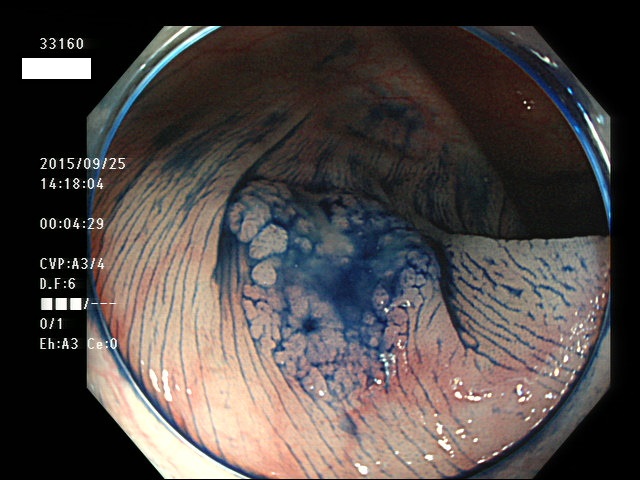

上記100名より抽出した平坦・陥凹型腺腫(=癌化の危険が高いが見落としやすい病変)の内視鏡写真